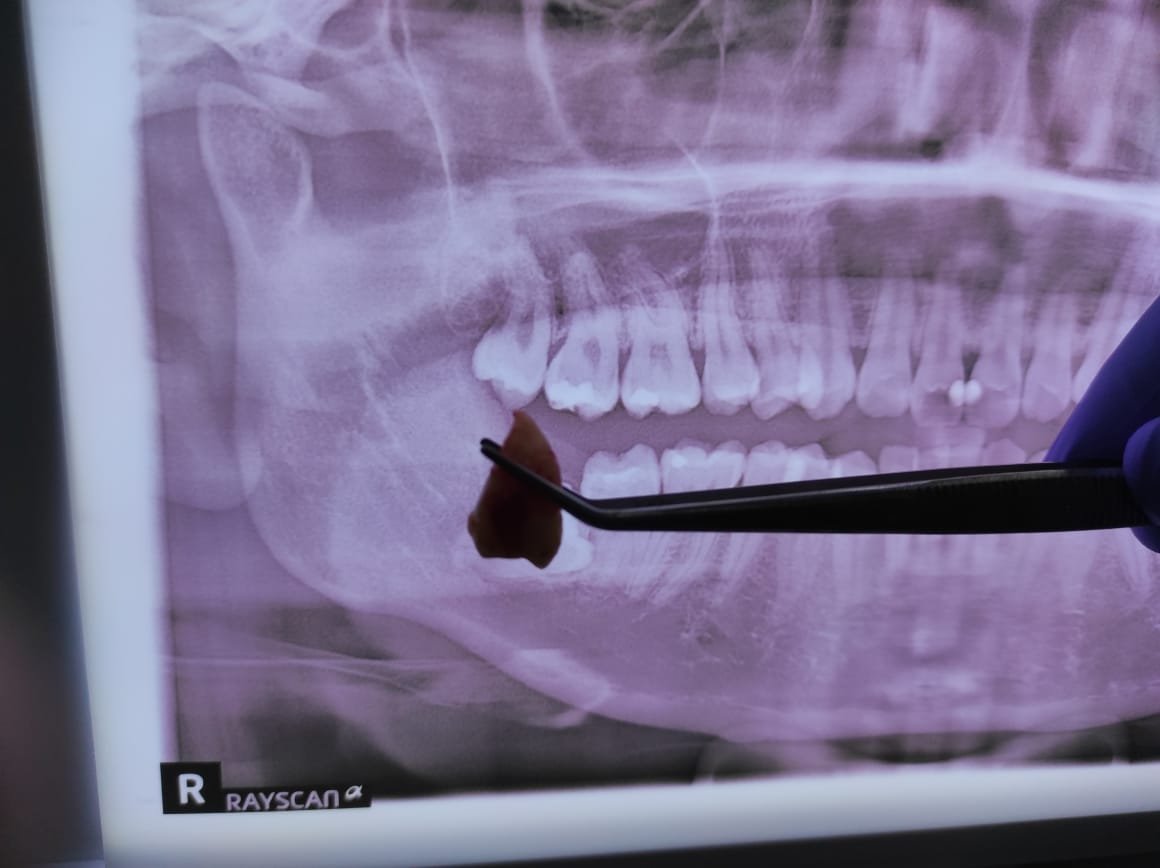

Prosedur odontektomi gigi bungsu di jakarta

Bagaimana Prosedur Odontektomi Dilakukan?

Dokter gigi bedah mulut melaksanakan odontektomi dengan beberapa langkah berikut:

1. Pemeriksaan awal

Dokter melakukan rontgen panoramic untuk melihat posisi gigi bungsu dan menilai kondisi pasien.

4. Pengangkatan gigi

Bila gigi sulit dicabut, dokter membaginya menjadi beberapa bagian lalu mengangkat potongan satu per satu.